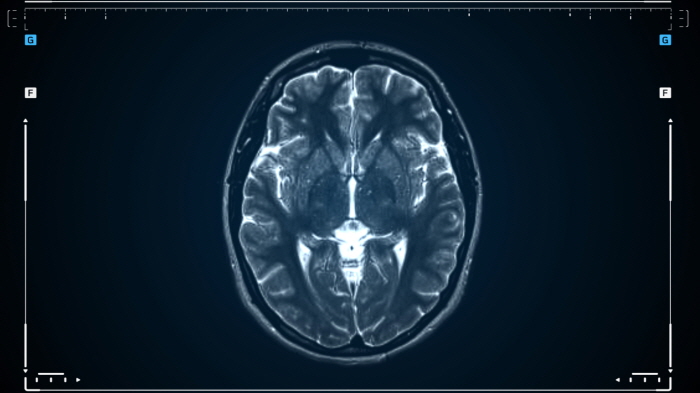

ㆍ MRI(자기공명영상): 뇌 속 유충의 위치와 크기를 정확히 확인할 수 있습니다.

ㆍ CT(컴퓨터 단층촬영): 유충에 의해 뇌에 생긴 병변을 확인합니다.

이 질환은 발작, 두통, 인지 기능 저하, 뇌수종 등 다양한 증상을 유발하며, 진단을 위해 MRI, CT 촬영 및 혈액 검사가 필요합니다.